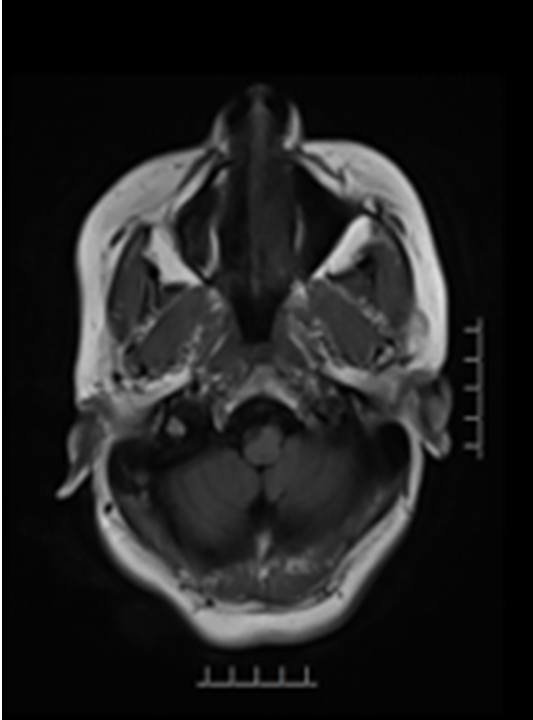

病历夹什么径技·第151期|串联营病历夹:京广连营_https://www.jmylbn.com_新闻资讯_第60张

结论:急诊MRI提示大脑右侧中动脉闭塞